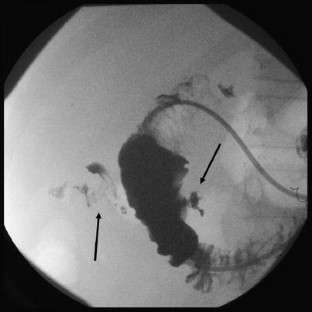

Fig. 2